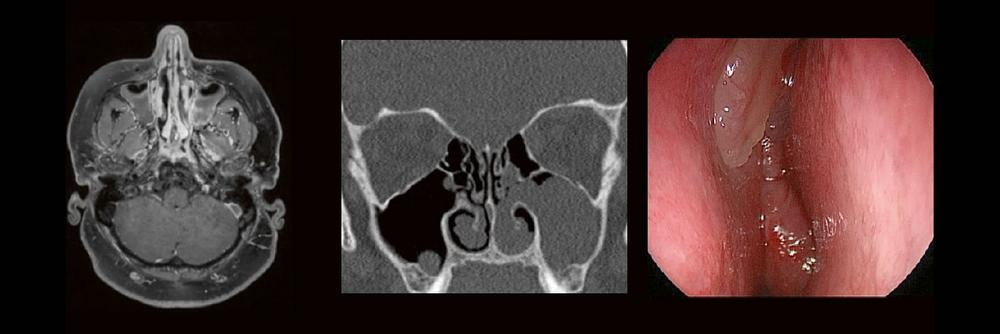

Die bildgebende HNO-Diagnostik macht es Anfängern nicht leicht. Die Anatomie ist komplex und weniger intuitiv als in anderen Körperregionen.

Normvarianten erschweren insbesondere in den Nasennebenhöhlen den Lernprozess. Sobald pathophysiologische Zusammenhänge verstanden und wichtige klinische Aspekte verinnerlicht wurden, gelingt es einen praxistauglichen, belastbaren Befund zu erstellen.

Begleiten Sie uns auf einer kooperativen Reise durch die NNH mit „Ach so!“-Garantie:

Gemeinsam mit einem HNO-Chirurgen werfen wir einen Blick IN die NNH – mal in grau, mal in Farbe. Denn alles fällt leichter, sobald man verstanden hat, warum man es tut.